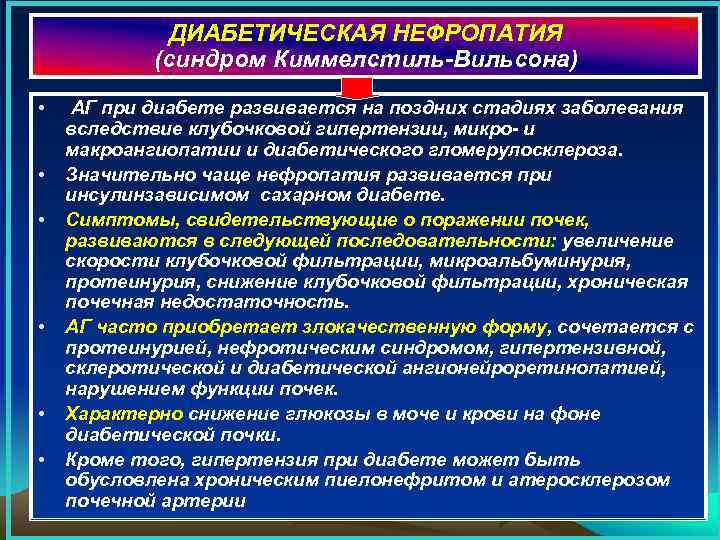

ДИАБЕТИЧЕСКАЯ НЕФРОПАТИЯ (синдром Киммелстиль-Вильсона) • • • АГ при диабете развивается на поздних стадиях заболевания вследствие клубочковой гипертензии, микро- и макроангиопатии и диабетического гломерулосклероза. Значительно чаще нефропатия развивается при инсулинзависимом сахарном диабете. Симптомы, свидетельствующие о поражении почек, развиваются в следующей последовательности: увеличение скорости клубочковой фильтрации, микроальбуминурия, протеинурия, снижение клубочковой фильтрации, хроническая почечная недостаточность. АГ часто приобретает злокачественную форму, сочетается с протеинурией, нефротическим синдромом, гипертензивной, склеротической и диабетической ангионейроретинопатией, нарушением функции почек. Характерно снижение глюкозы в моче и крови на фоне диабетической почки. Кроме того, гипертензия при диабете может быть обусловлена хроническим пиелонефритом и атеросклерозом почечной артерии

ДИАБЕТИЧЕСКАЯ НЕФРОПАТИЯ (синдром Киммелстиль-Вильсона) • • • АГ при диабете развивается на поздних стадиях заболевания вследствие клубочковой гипертензии, микро- и макроангиопатии и диабетического гломерулосклероза. Значительно чаще нефропатия развивается при инсулинзависимом сахарном диабете. Симптомы, свидетельствующие о поражении почек, развиваются в следующей последовательности: увеличение скорости клубочковой фильтрации, микроальбуминурия, протеинурия, снижение клубочковой фильтрации, хроническая почечная недостаточность. АГ часто приобретает злокачественную форму, сочетается с протеинурией, нефротическим синдромом, гипертензивной, склеротической и диабетической ангионейроретинопатией, нарушением функции почек. Характерно снижение глюкозы в моче и крови на фоне диабетической почки. Кроме того, гипертензия при диабете может быть обусловлена хроническим пиелонефритом и атеросклерозом почечной артерии